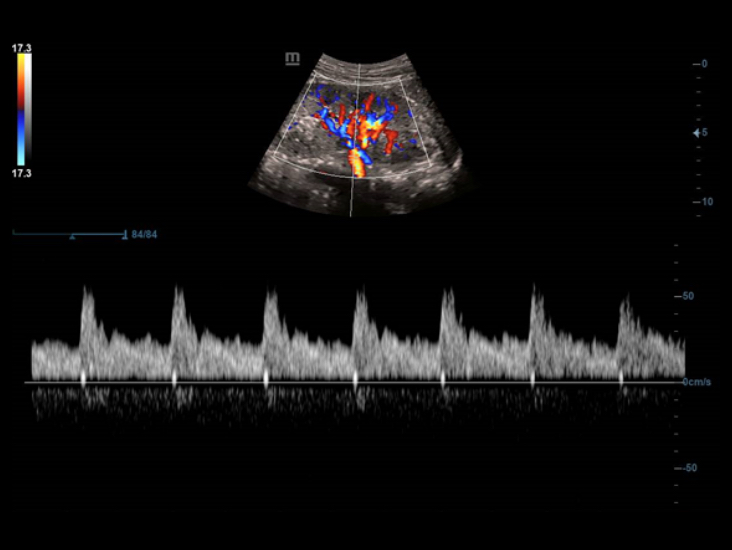

Funkcja Smart Track zapewnia szybk? i inteligentn? optymalizacj? obrazów naczyń krwiono?nych zaledwie po jednym klikni?ciu. Umo?liwia optymalizacj? w trybach Dopplera Kolorowego, Power Dopplera i Dopplera spektralnego PW poprzez samodzieln? detekcj? naczynia i skrócenie czasu niektórych etapów badania. W ten sposób cykl czynno?ci podczas badania naczyń krwiono?nych zosta? uproszczony z jednoczesnym zachowaniem optymalnego obrazowania.